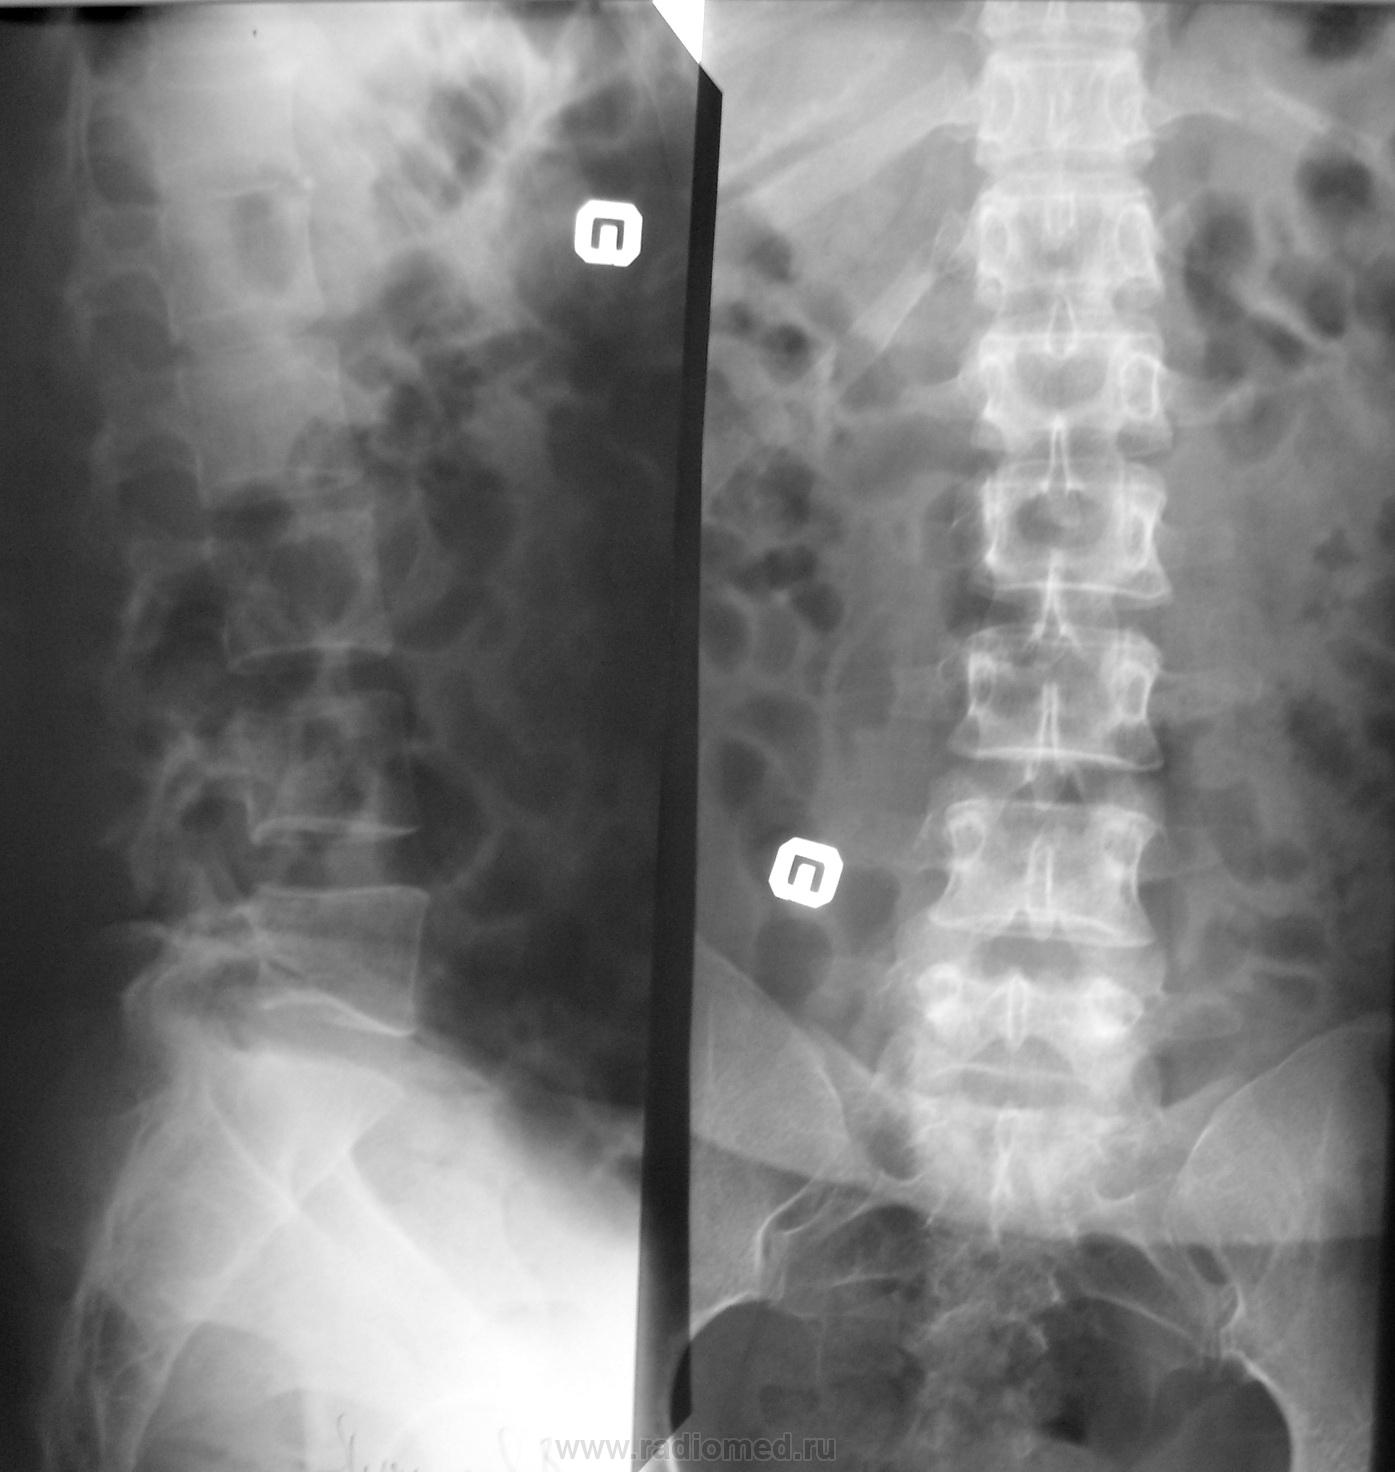

Молодая женщина упала на лестнице. Поставлена задача исключить перелом L1. Засомневался я. Что скажите уважаемые коллеги?

Боковая для верхнепоясничного не совсем в "адеквате"...потому то и сомнения берут...переснимите прицельно, если клинически на то есть основание....

Игорь Артурович!Д12-подозрительно уплощен и зам. пласт. уплотнены!?

Может быть апофизеолиз L1?

Для начала надо переснять боковую проекцию, чтобы L1 был в оптимальных условиях видения. А то это гадание на кофейной гуще получается, а от этого заключения будет зависить и больничный и тактика лечения.

Если поставлена задача исключить перелом L1, то с диафрагмированием снять прицельно L1. И либо наладить центратор, либо показать лаборанту куда центровать...